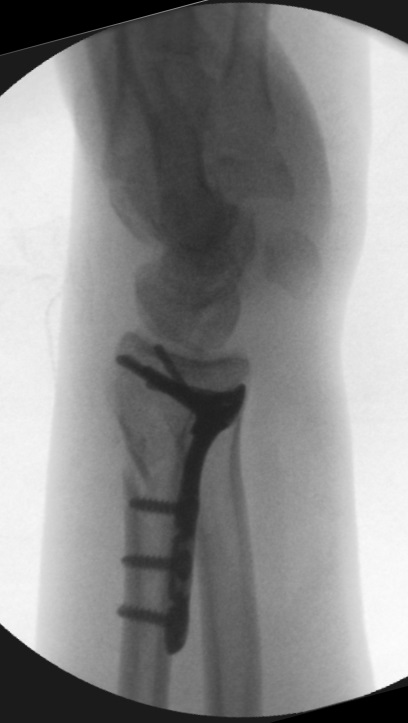

Välplacerad DVR-platta. Sidobilden är inte rak.